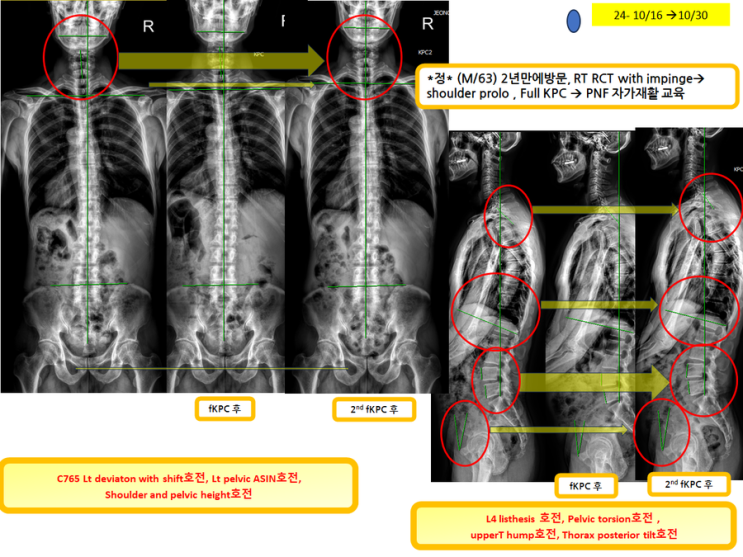

우측어깨 통증으로 2번째 full KPC 시행하신 분(녹는실KPC치료는 엑스레이 호전을 10분만에 확인)

우측어깨 통증으로 2번째 full KPC 시행하신 분 (녹는실KPC치료는 엑스레이 호전을 10분만에 확인) ...